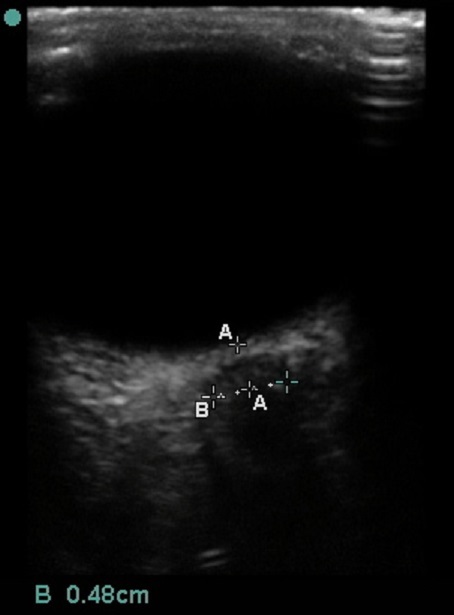

Ocular Optic Nerve Sheath Diameter Image